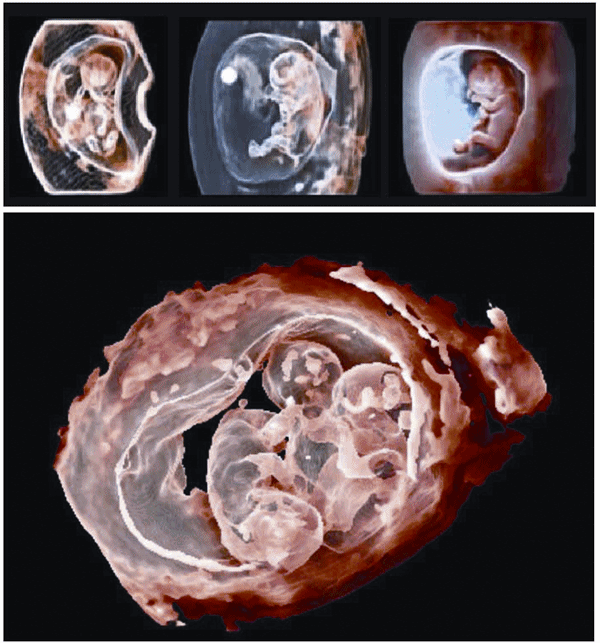

TrueVue – Making images more realistic

TrueVue creates images that are more realistic, appealing and at the same time providing more clinical information. TrueVue, with its virtual light source, is a proprietary advanced 3D ultrasound display method that delivers amazing lifelike 3D ultrasound images and gives the operator the ability to move the light source anywhere in the 3D volume.

GlassVue – Going beyond the surface

GlassVue goes beyond the surface to reveal bone, organs, and other internal structures.

GlassVue, with internal light source, provides an early, more transparent view of the foetal anatomy than traditional ultrasound.